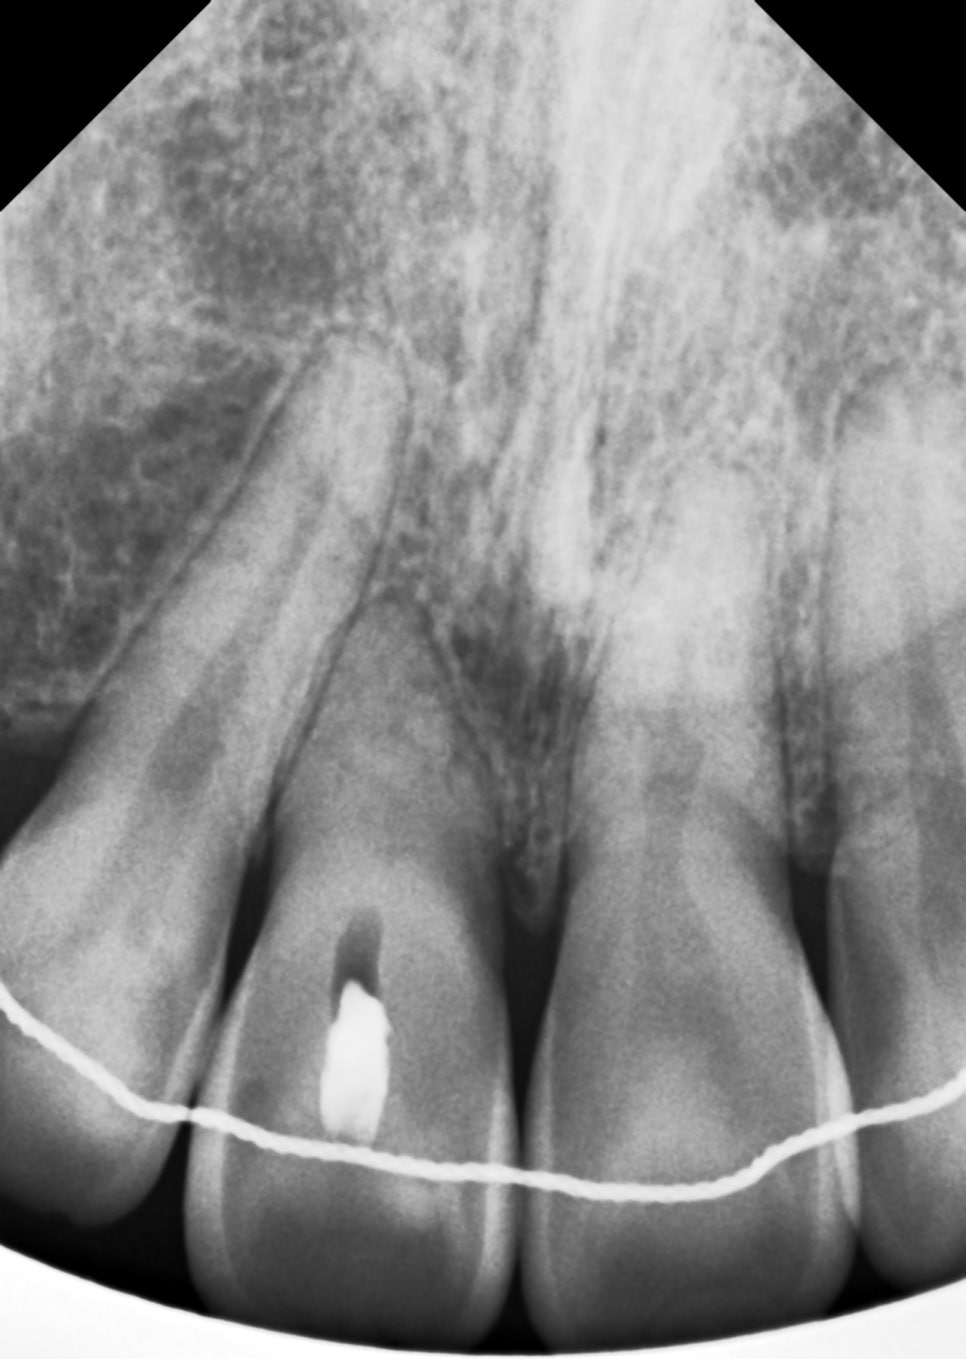

확인해 보니 교정 후

해당 치아의 뿌리가 많이 흡수된

양상이 보였어요.

그렇지만 당장 빼기에는

너무 아까웠죠...

저도 최종적으로 레진 비니어를 통해

치료하기로 계획했지만,

그 전에 실활치 미백을 통해 바탕색을

미리 밝게 만들어야 한다고 진단했습니다.

물론, 일반적인 케이스에 비해

색상이 완벽하게 돌아오지

않을 수 있지만

색상이 지금보단 밝아질 수 있다고

판단했어요.